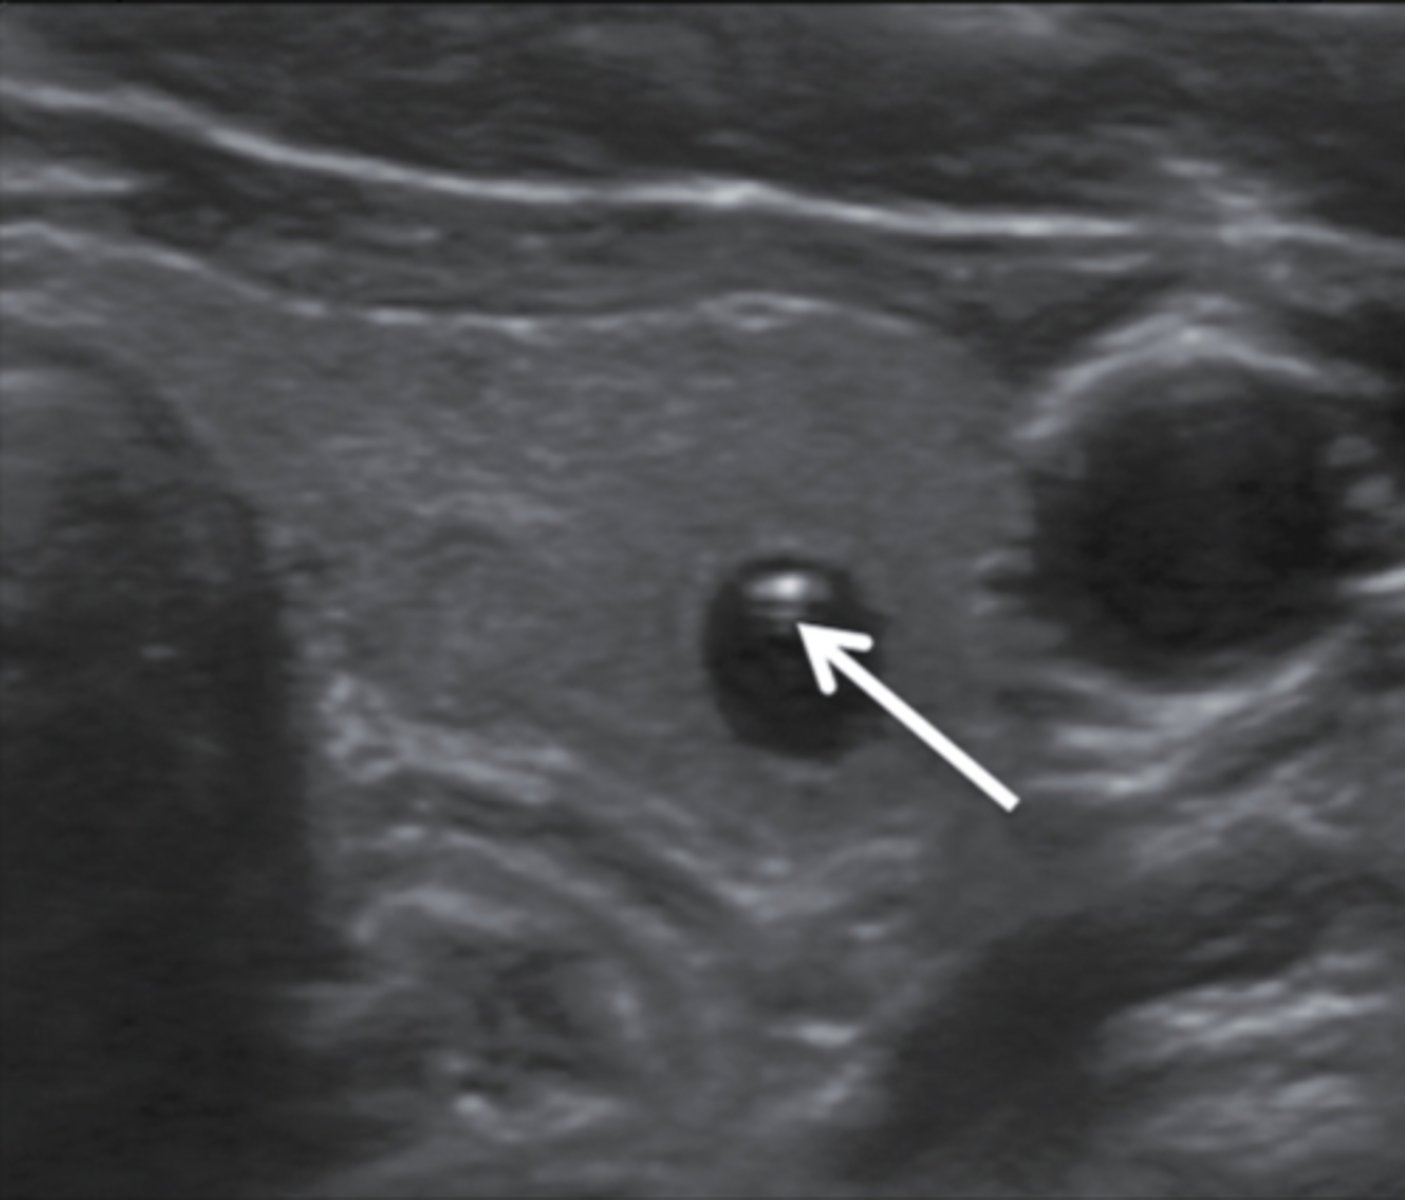

13. What does the structure noted in Figure 12-28 demonstrate?

a. Colloid cyst

b. Follicular carcinoma

c. Papillary carcinoma

d. Isoechoic thyroid nodule